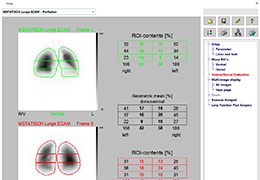

ANYTHINK 经导管主动脉瓣膜置换术分析系统